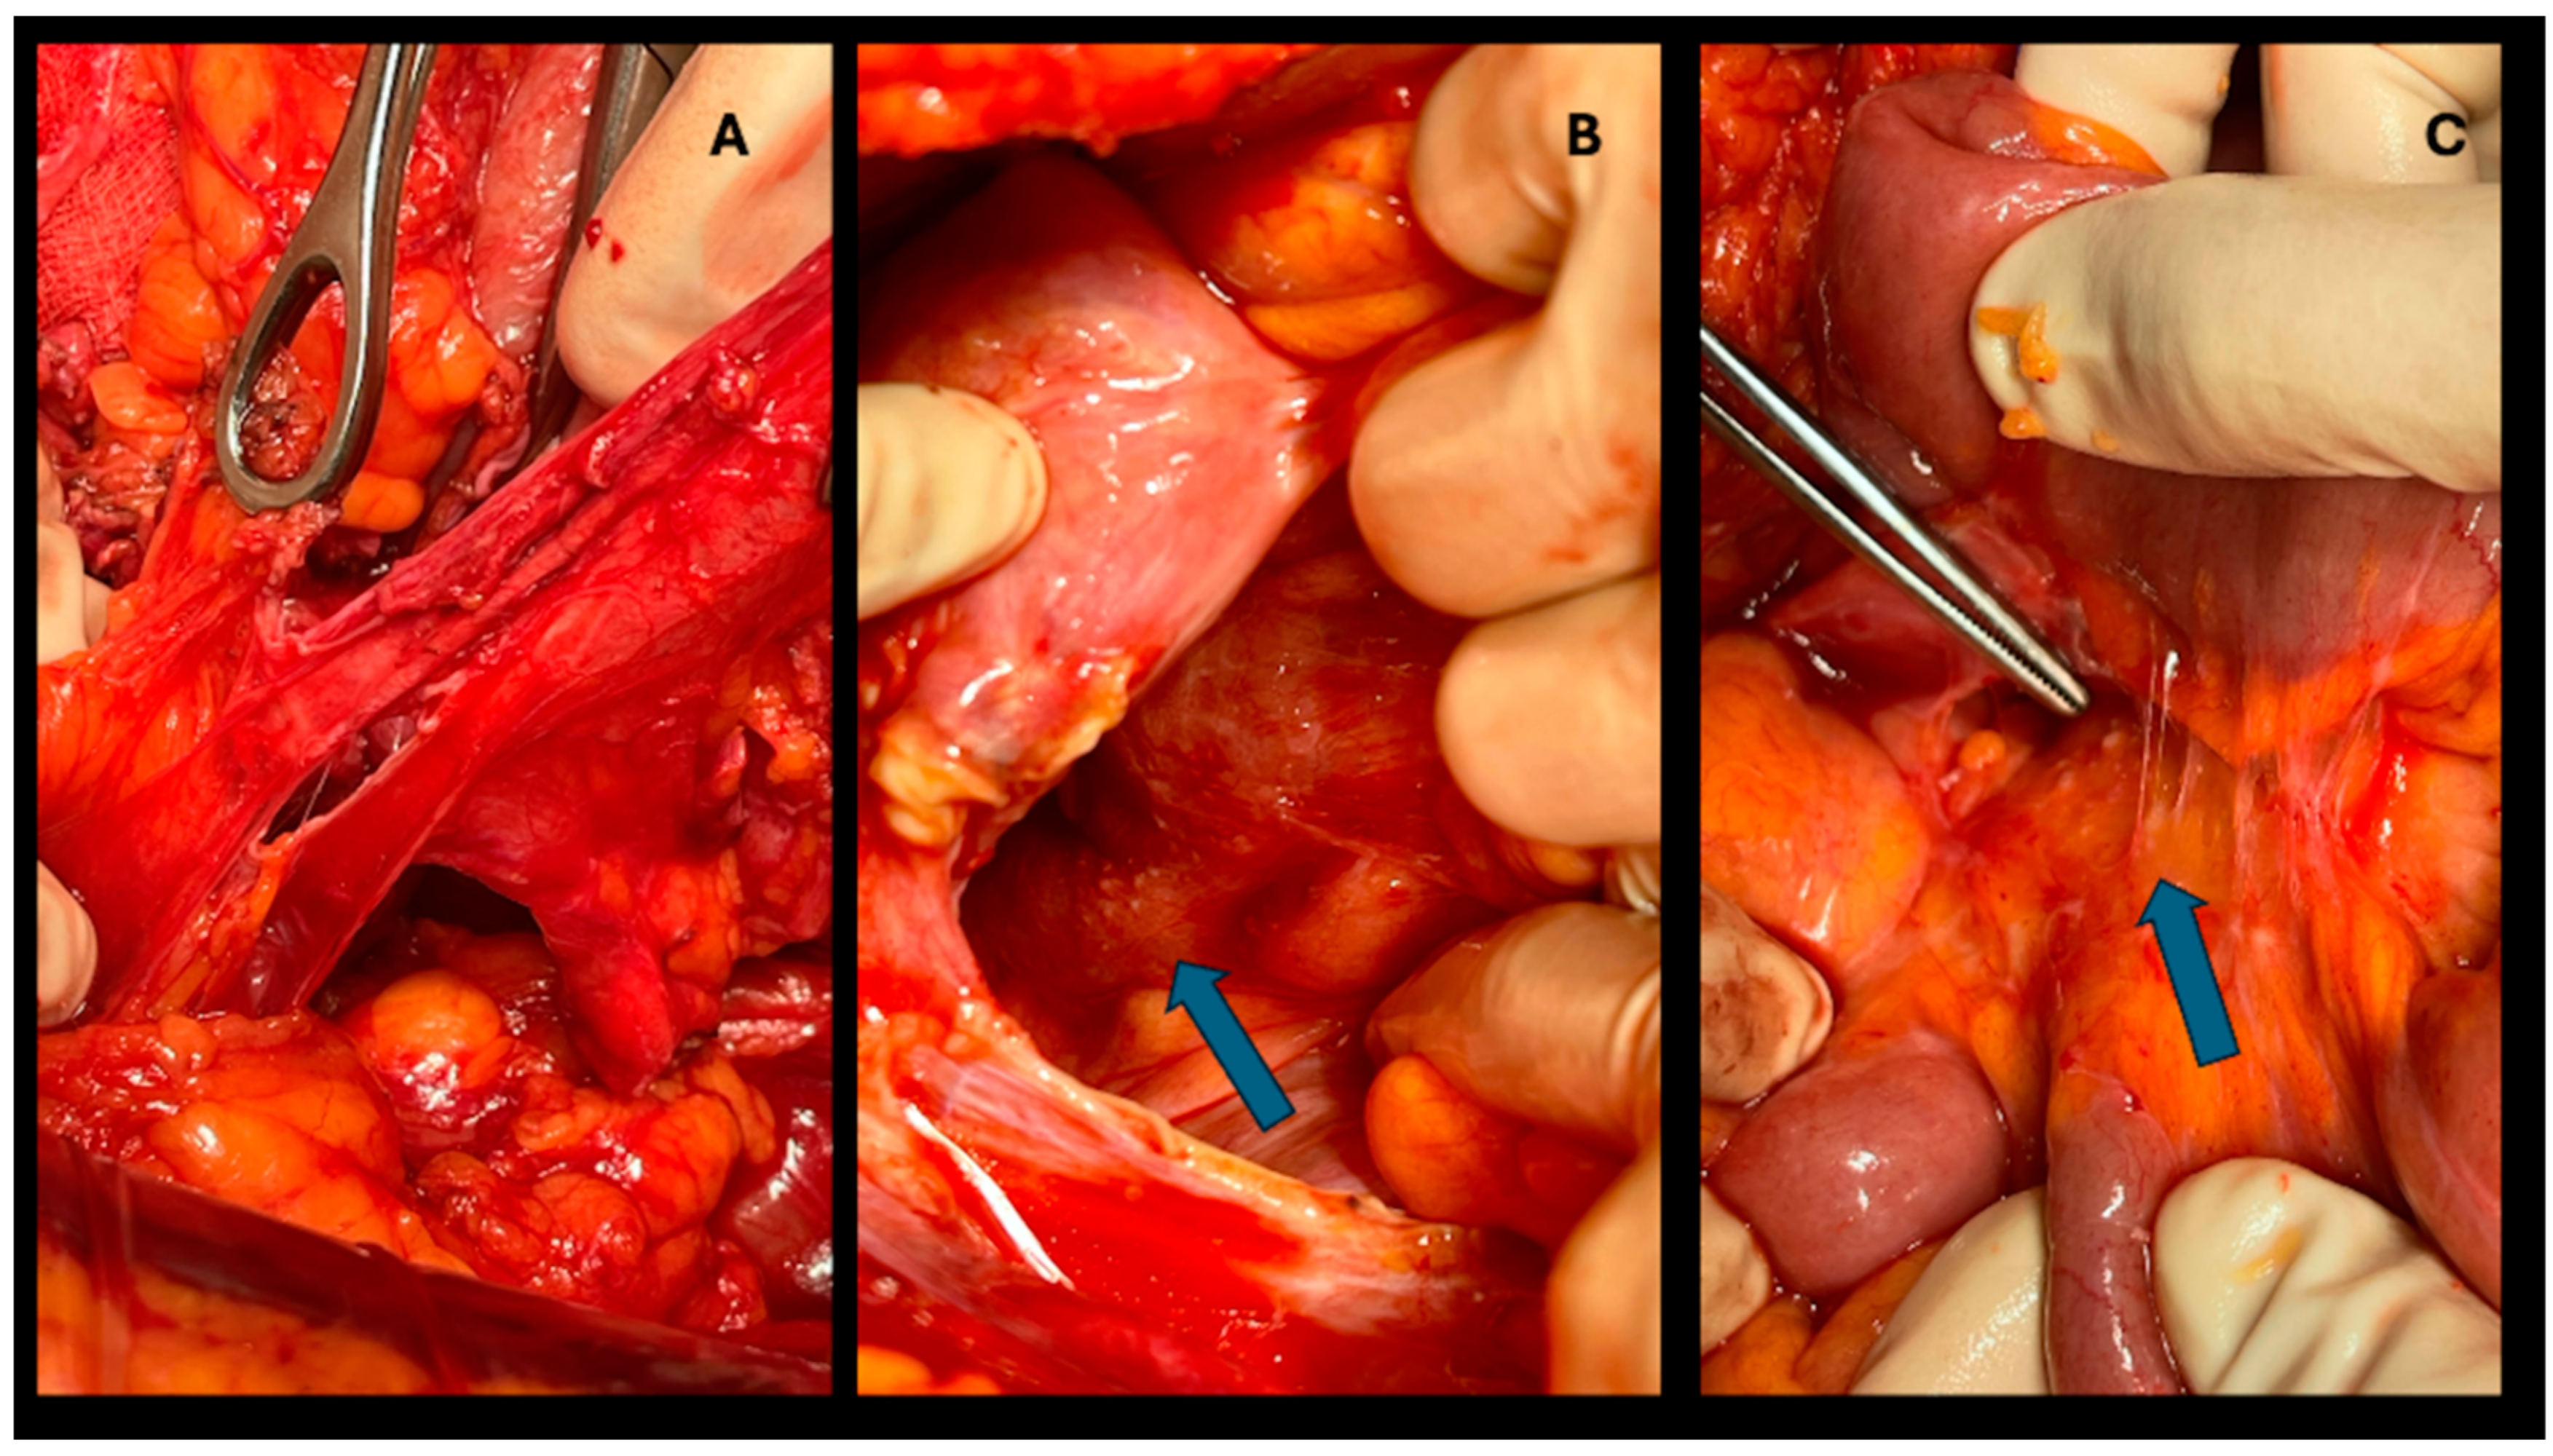

Figure 2. CRS+HIPEC procedure. A: Peritoneum resection. B, C: the arrows point the peritoneal metastases.

Hepatic resections were all performed in an open setting. The type of surgery to be performed was decided based on imaging examinations (CT, MRI, or both), anatomical complexity, and whether CRS+HIPEC was performed concomitantly. Operations performed included major hepatectomy (three or more liver segments; n=6), minor hepatectomy (less than three segments; n=6), atypical resection (n=26), and double-vein embolization (n=2) [11]. (Figure 1) (Figure 2) (Figure 3)